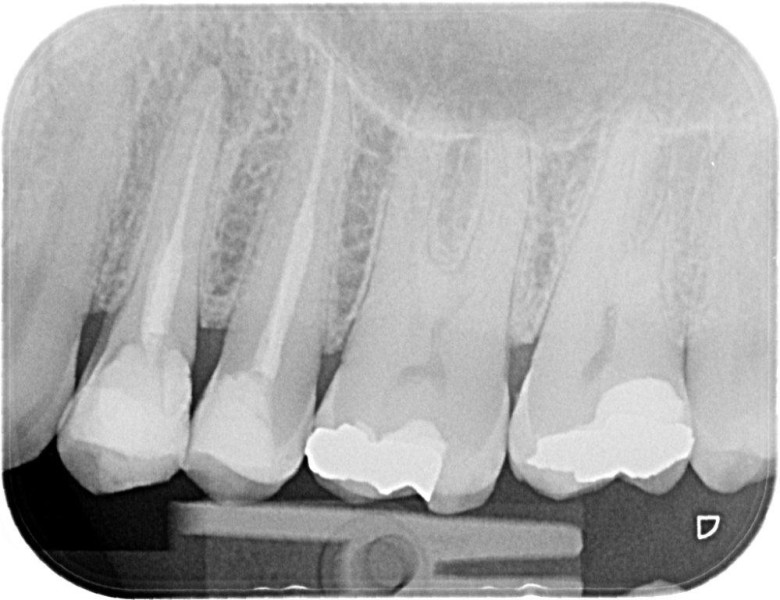

Premolar retreatment